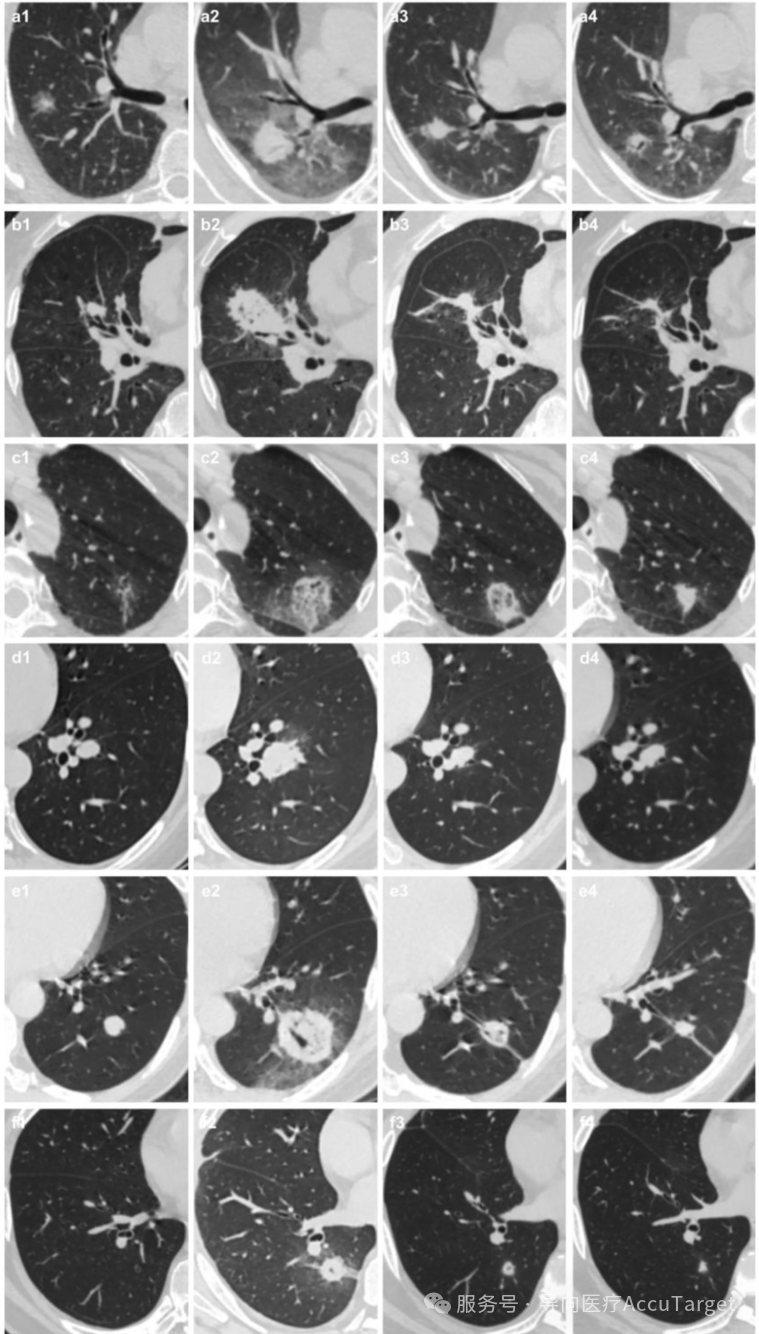

▲ 6例冷冻消融术前后胸部CT影像。(x1-x4) 术前、术后≤3天、1个月及3个月的胸部CT。